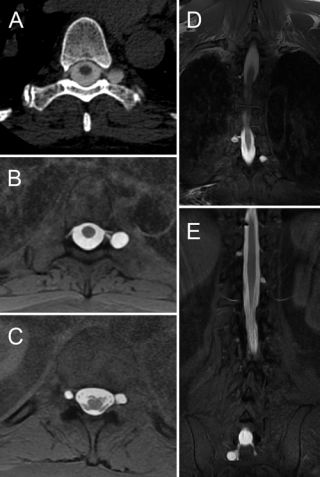

13.椎动脉夹层动脉瘤行血管内弹簧圈栓塞治疗后发生延髓梗死的预测因素。

Predictive factors of medullary infarction after endovascular internal trapping using coils for vertebral artery dissecting aneurysms.

PMID: 28799869 DOI: 10.3171/2017.2.JNS162916

椎动脉夹层动脉瘤(vertebral artery dissecting aneurysms, VADAs)首选血管内弹簧圈栓塞治疗,但有发生延髓梗死的风险。研究纳入100例血管内弹簧圈栓塞的椎动脉夹层动脉瘤患者,30例发生延髓梗死,其中27例为延髓后外侧,3例为延髓前内侧。对延髓梗死患者进行临床分析,结果显示:栓塞长度并非延髓梗死发生的危险因子,而是夹层动脉瘤所在的解剖位置。栓塞VA远端动脉瘤发生的延髓梗死的风险低,但患者的症状重;保护脊髓前动脉的起始部可以降低延髓梗死风险;栓塞的长度越短,发生并发症的可能性就越低,但仍不能防止梗死的发生。对于存在严重缺血并发症的破裂型VADAs(如对侧VA发育不良、病变累及小脑后下动脉或脊髓前动脉不适宜栓塞治疗)或未破裂型VADAs者可以考虑血管重建治疗。